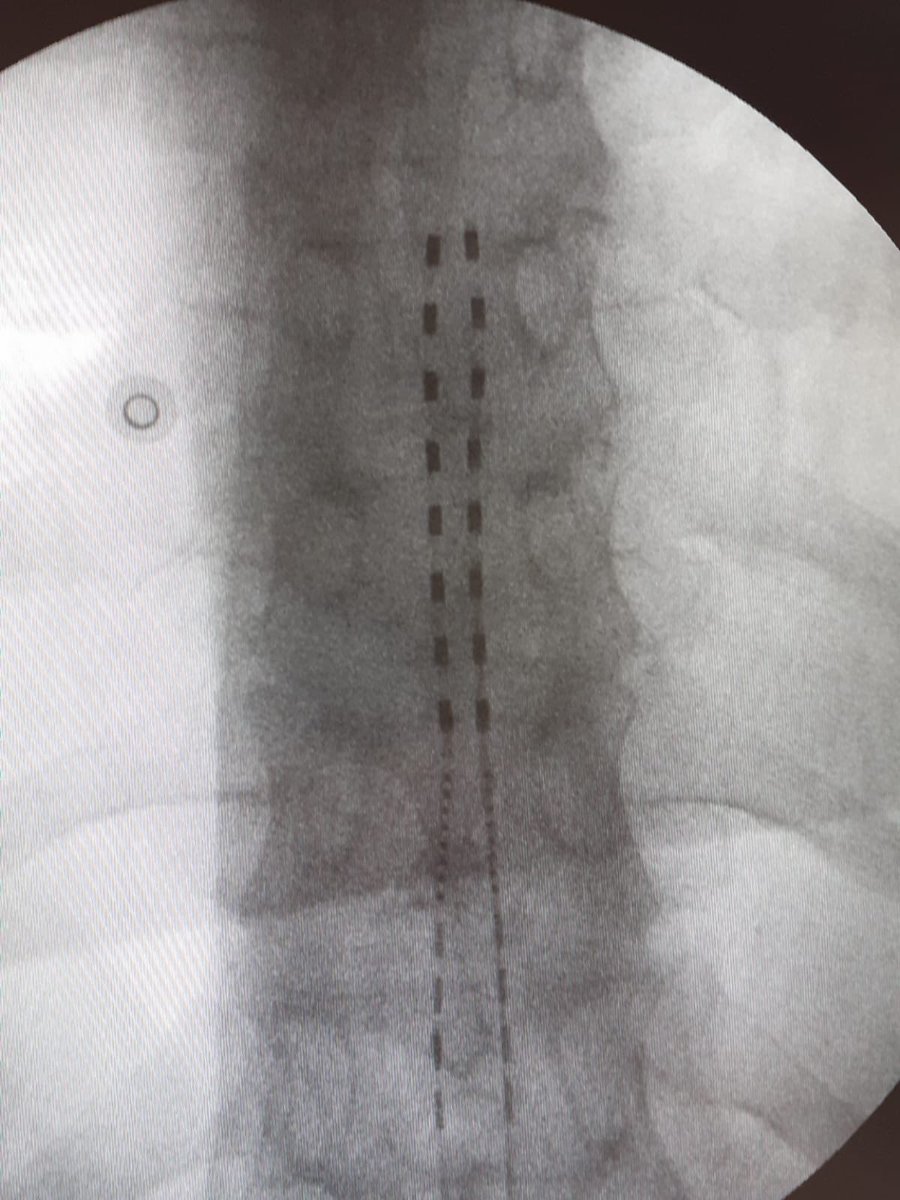

HF10 therapy for low back pain caused by degenerative spinal stenosis

@Nevro_HF10#spinalcordstimulation#spinalstenosis#chronicpainmanagement@HMHOSPITALESpic.twitter.com/rXF0nCrBRM